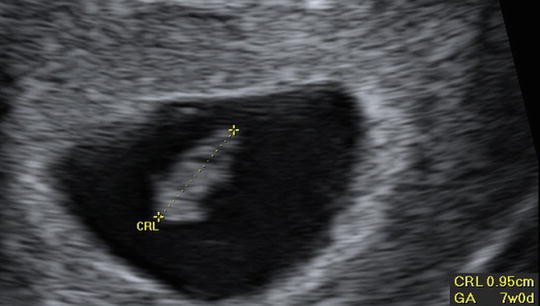

2 . If there is more than one first-trimester scan with a mean sac diameter or crown-rump length measurement, the earliest ultrasound with a crown-rump length equivalent to at least 7 weeks (or 10 mm) should be used to determine the gestational age (III B) . Ideally the dating ultrasound is at least 7 weeks or 10 mm of gestation .

Known conception date using reproductive technologies . 2) Use the earliest ultrasound (TA or TV) estimate if between 7 (CRL > 10 mm) and 22+6 weeks of gestation . 3) First trimester US is the most accurate, so whenever possible, get a dating scan . 4) After 23 weeks, can use US or clinical judgement . 5) Clinical judgement may still be needed, but . . .